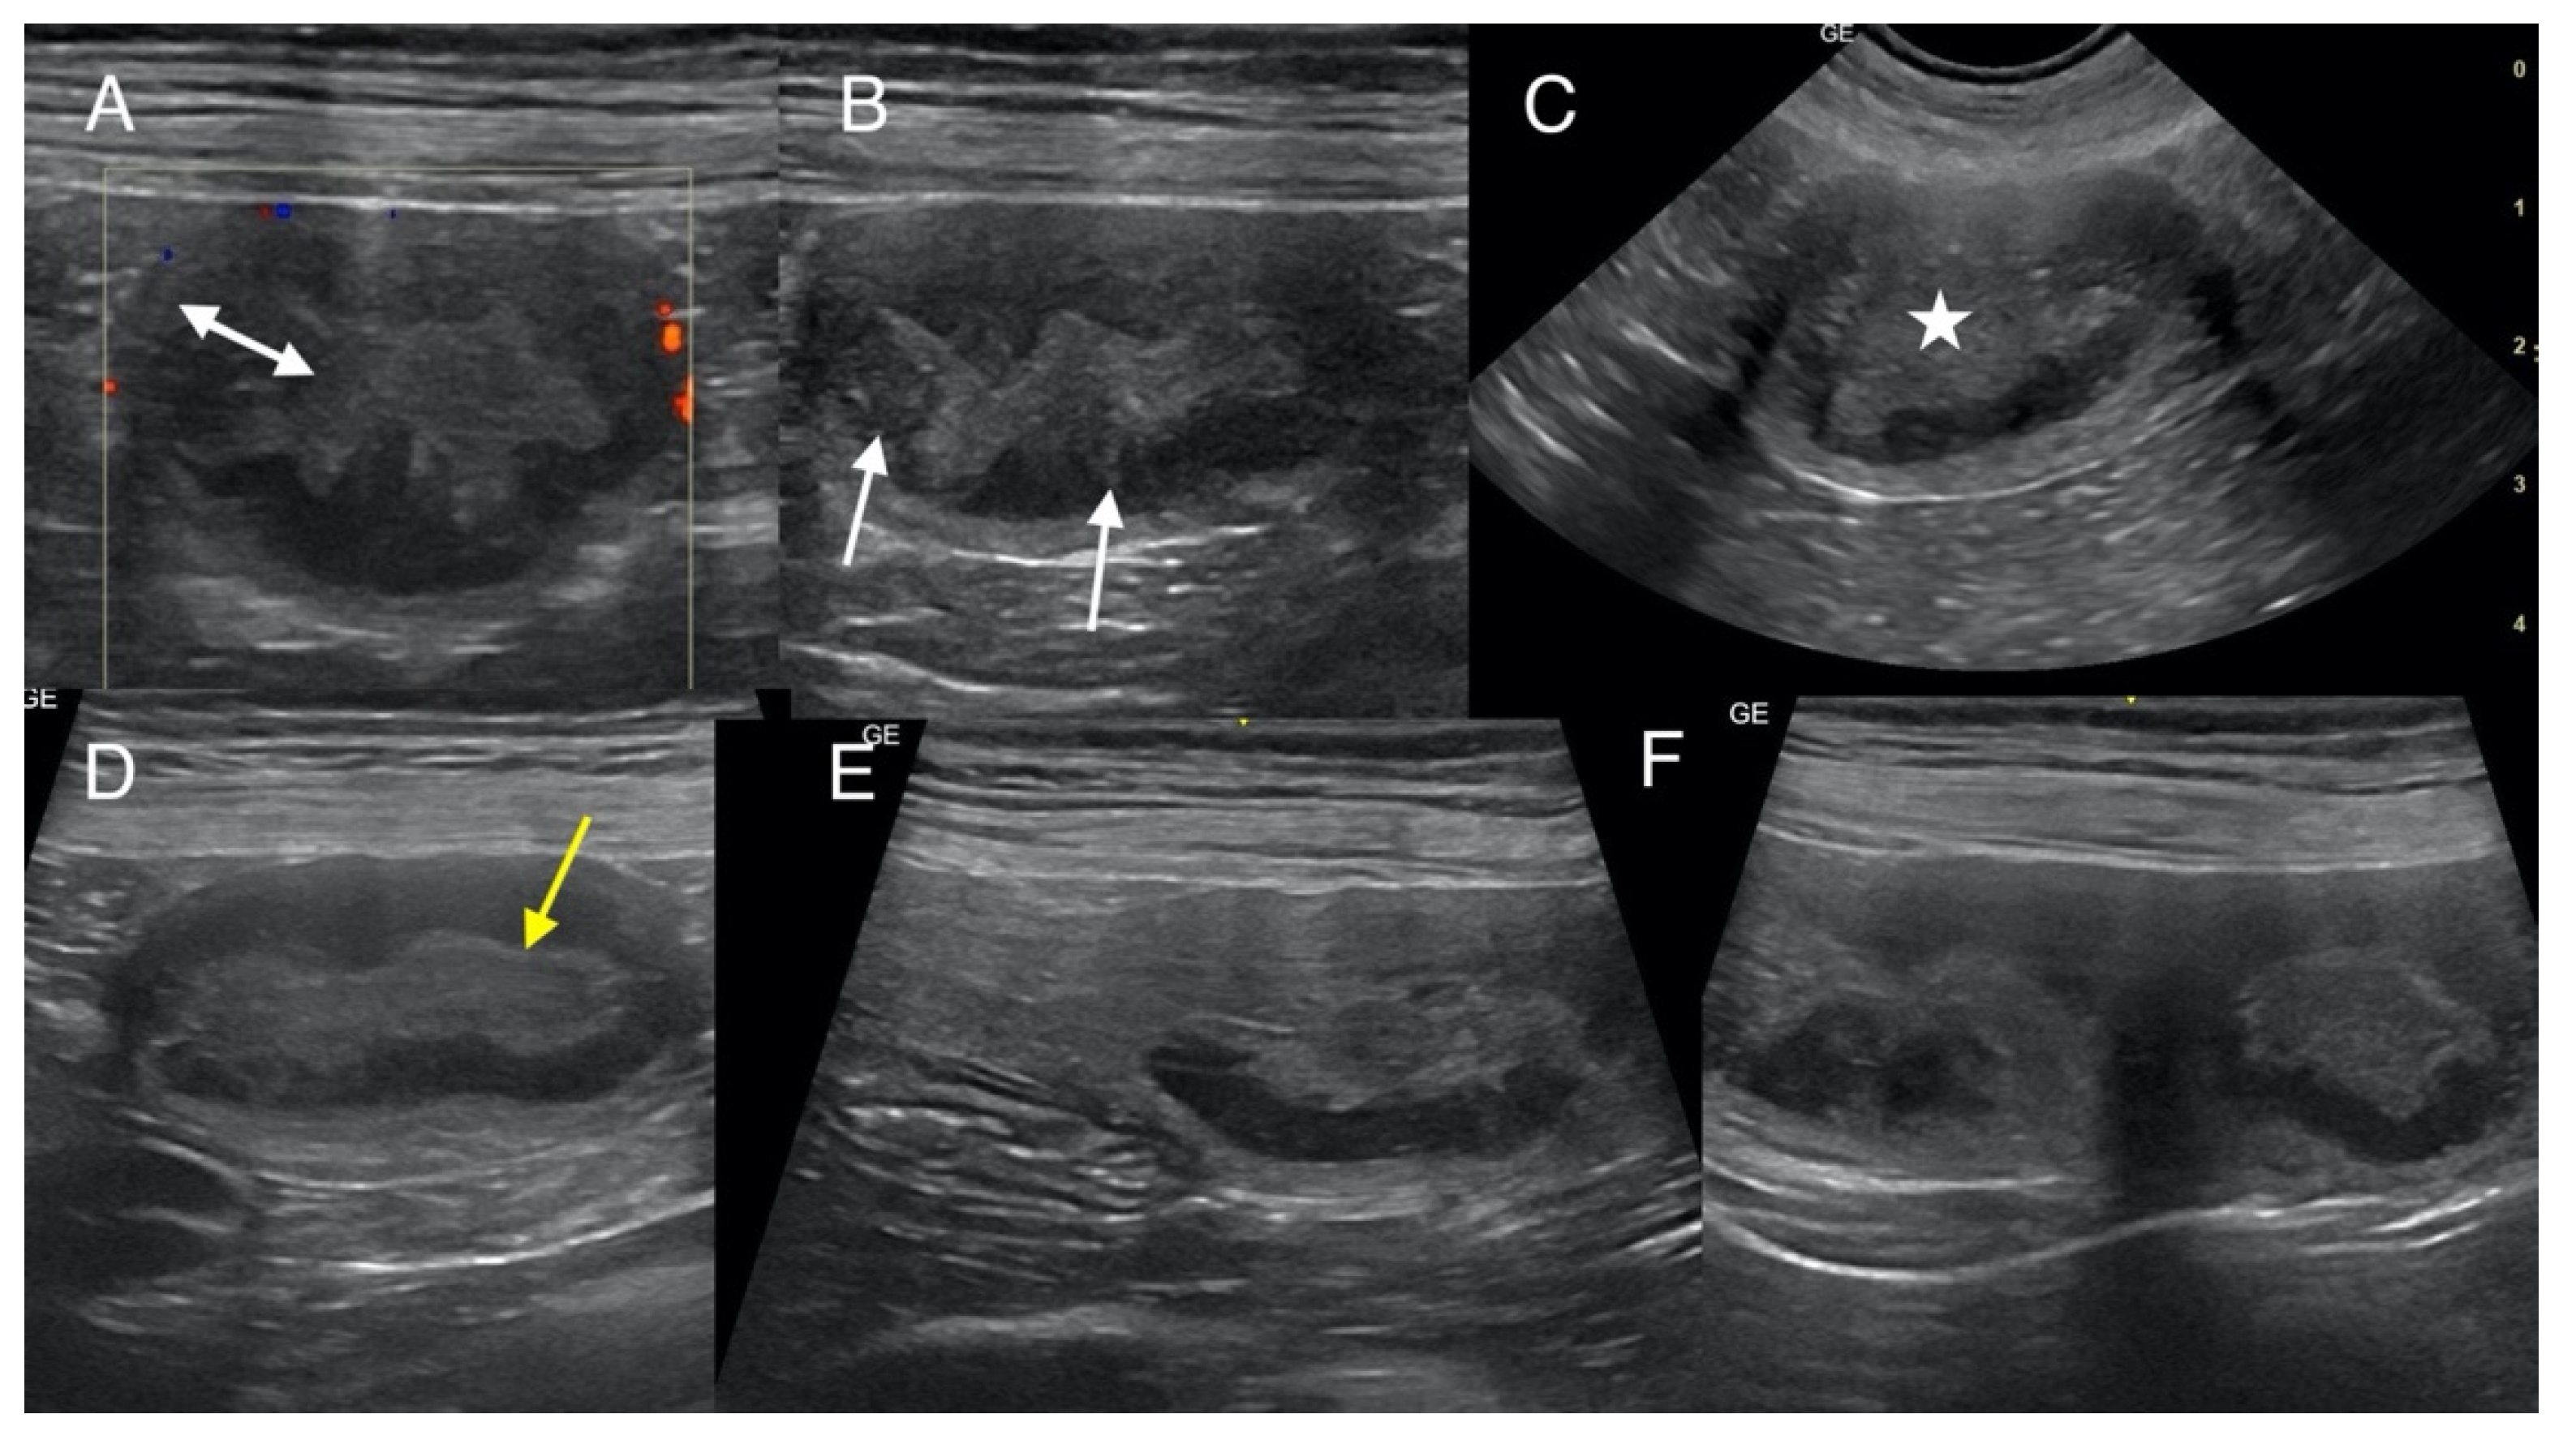

The owners did not consent to any additional tests, including blood tests, urinalysis, or screening for infectious agents such as Brucella canis. A follow-up examination of the uterus, ovaries, and the entire abdominal cavity was performed a week later (32nd day post-mating) by specialists in ultrasonography and reproduction using a microconvex probe (6–10 MHz; GE Healthcare, Chicago, IL, USA) and a linear probe (5–13 MHz; GE Healthcare, Chicago, IL, USA) in B-mode (Versana Premier; GE Healthcare, Chicago, IL, USA). Multiple ampullary dilations in both uterine horns were confirmed. Next, ultrasound evaluation was conducted on the 38th day post-breeding. Again, focal dilations were observed along both uterine horns, manifesting as oval thickening measuring 2.0–2.6 × 3.0–3.6 cm. Six lesions were present in the left uterine horn, four of which were closely connected and poorly separated, one located nearby, and another near the uterine body. Two thickenings were visualized in the right horn, closer to the ovary, separated by an unaffected short segment of uterine tissue. The altered segments exhibited a layered architecture, and the endometrium was noticeably thickened to 0.3–0.7 cm. The mucosal surface appeared wavy, with irregular segmentations and a hyperechoic surface, and demonstrated apparent depressions best visualized in transverse scans performed by linear and microconvex probes (Figure 1). The mucosal layer was hypoechogenic and predominantly homogeneous to slightly heterogeneous; segmentally, irregular hyperechoic points and weakly defined hyperechoic linear bands were seen. A small but variable amount of condensed hyperechoic fluid was seen in the uterine lumen. The segments between the lesions were uniform but only slightly thickened (up to about 1 cm). No endometrial cysts were observed. Neither increased mesenteric reaction nor free fluid was found around the uterine horns. The medial iliac lymph nodes were not enlarged. The Doppler examination showed vascularization originating from the uterine vessels (presumably both veins and arteries) encasing the external surface of the ampullary thickenings (Figure 1A). Both ovaries were enlarged (left: 1.2 × 2.2 cm, right: 1.4 × 2.4 cm), exhibiting characteristics typical of diestrus, with a corrugated surface and the presence of hypoechogenic areas indicative of corpora lutea. In the differential diagnosis, the following conditions were considered: possible embryonic resorption, endometrial inflammatory remodeling, focal hyperplasia with fluid retention, and pseudo-placental proliferation.

Figure 1.

Ultrasound scans of the uterus obtained using a linear probe on the 32nd (A,B,D–F) and microconvex probe on the 38th (C) day after mating. The examination revealed ampullary dilatation of the uterine horns; transverse sections (A–C) and sagittal sections (D–F). Thickening and irregularities of the endometrium are visible (double-headed arrow), as well as few hyperechoic foci and streaks (arrows). The inner layer of the endometrium adjacent to the lumen is hyperechoic (yellow arrow). The presence of hyperechoic fluid content can be seen in the lumen in the thickened part of the uterus (asterisk). Visible vascularization of the uterine wall (A). The image of the left horn shows adjacent areas of thickening (F) without narrowing, and in the right horn, there is a clear demarcation from the normal part of the horn (E).